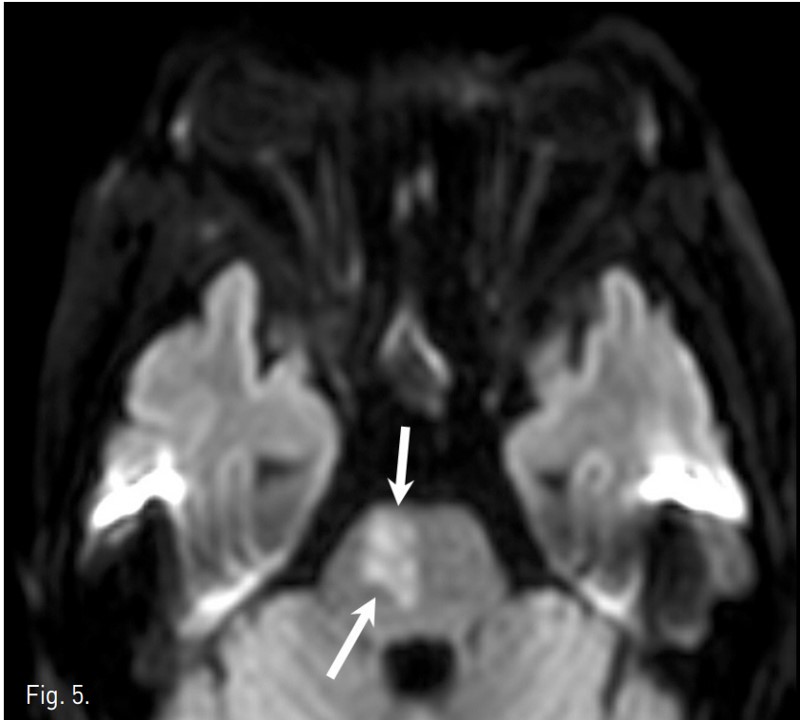

Fig. 5.

Fig. 5. Diffusion weighted image of brain MRI demonstrates a wedge shaped lesion with high signal intensity in the right paramedian aspect of the upper pons(arrows).